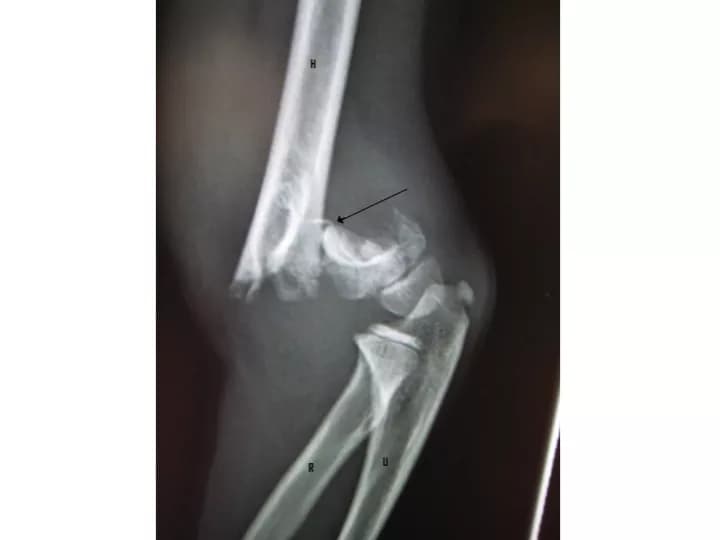

An elbow fracture occurs, when one of the bones of the elbow joint is broken. Elbow Fractures in Children are amongst the most common type of fractures observed in children and adolescents. Test your knowledge of this medical condition by taking our quiz!